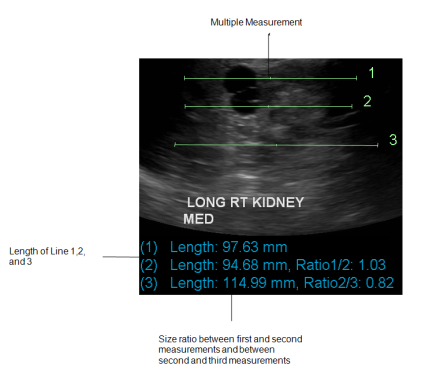

For each additional measurement you create, the ratio between measurements appears. The new measurement remains selected until you click in the viewport.

Multiple measurements